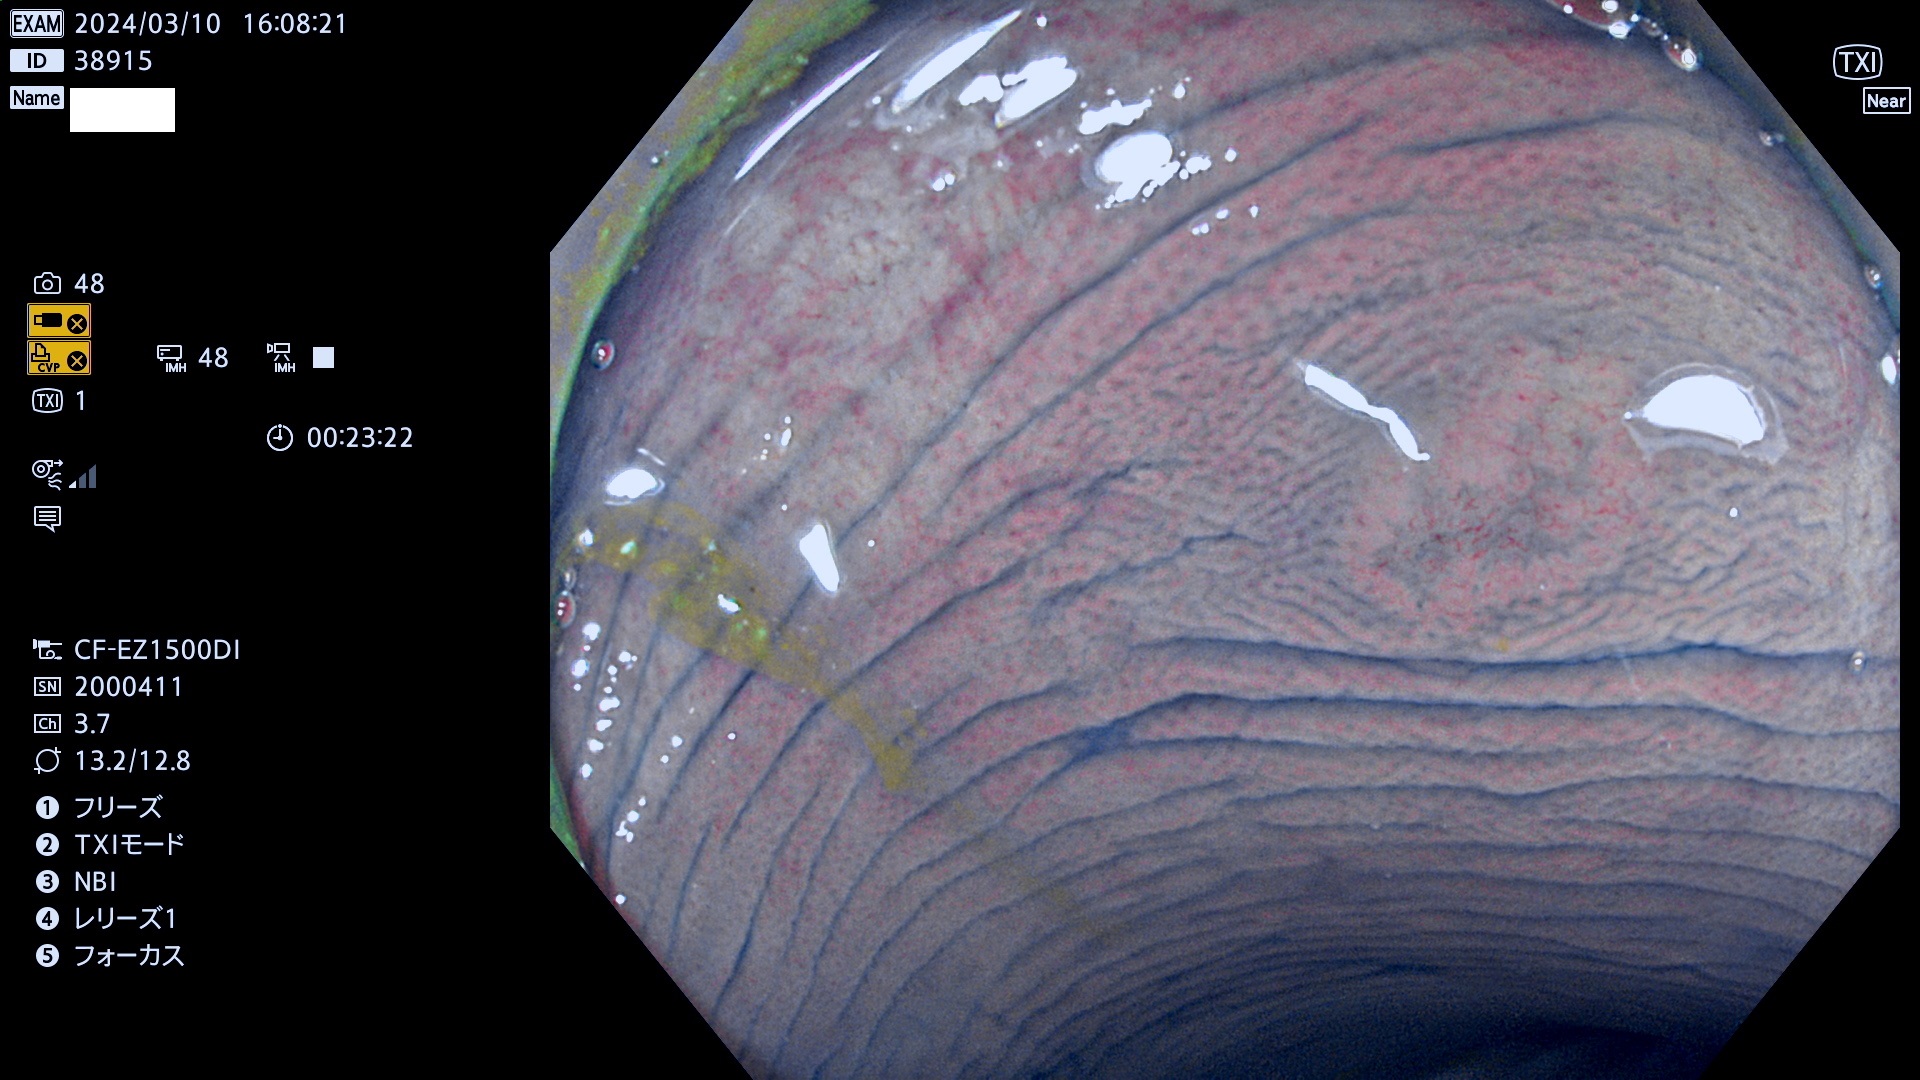

今週のUb、Uc型腺腫

表面型腺腫(Flat Adenoma)の中で、完全に平坦な物をUb、陥凹している物をUcと呼びます。平坦隆起型(Ua)よりも、発見が難しく危険な病変です。

毎週の検査(木・金・土・日)に発見されたUb、Uc型・腺腫を、その週の日曜の夜にUPし1週間、提示します。

抽出の対象期間 2024年3月7日(木)〜3月10(日)の4日間(40件の検査)6件 (6/40=13%)